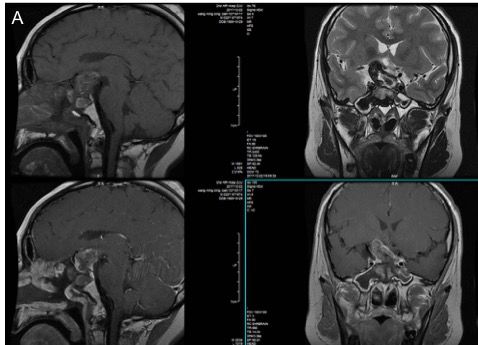

垂体增强MRI:鞍区见巨大类圆形混杂异常信号病灶,界限清,大小约39.7mm*28.4mm*33.2mm,以等短T1、稍长T2信号为主,病灶内信号不均匀,增强扫描病灶边缘局部轻度强化。垂体明显受压变扁,垂体柄及视交叉显示不清。第三脑室前下部受压,且鞍底骨质受压变薄。双侧海绵窦区结构未见异常 (图2)。

图2. 垂体MRI检查,显示鞍内肿瘤向鞍上发展,边界清